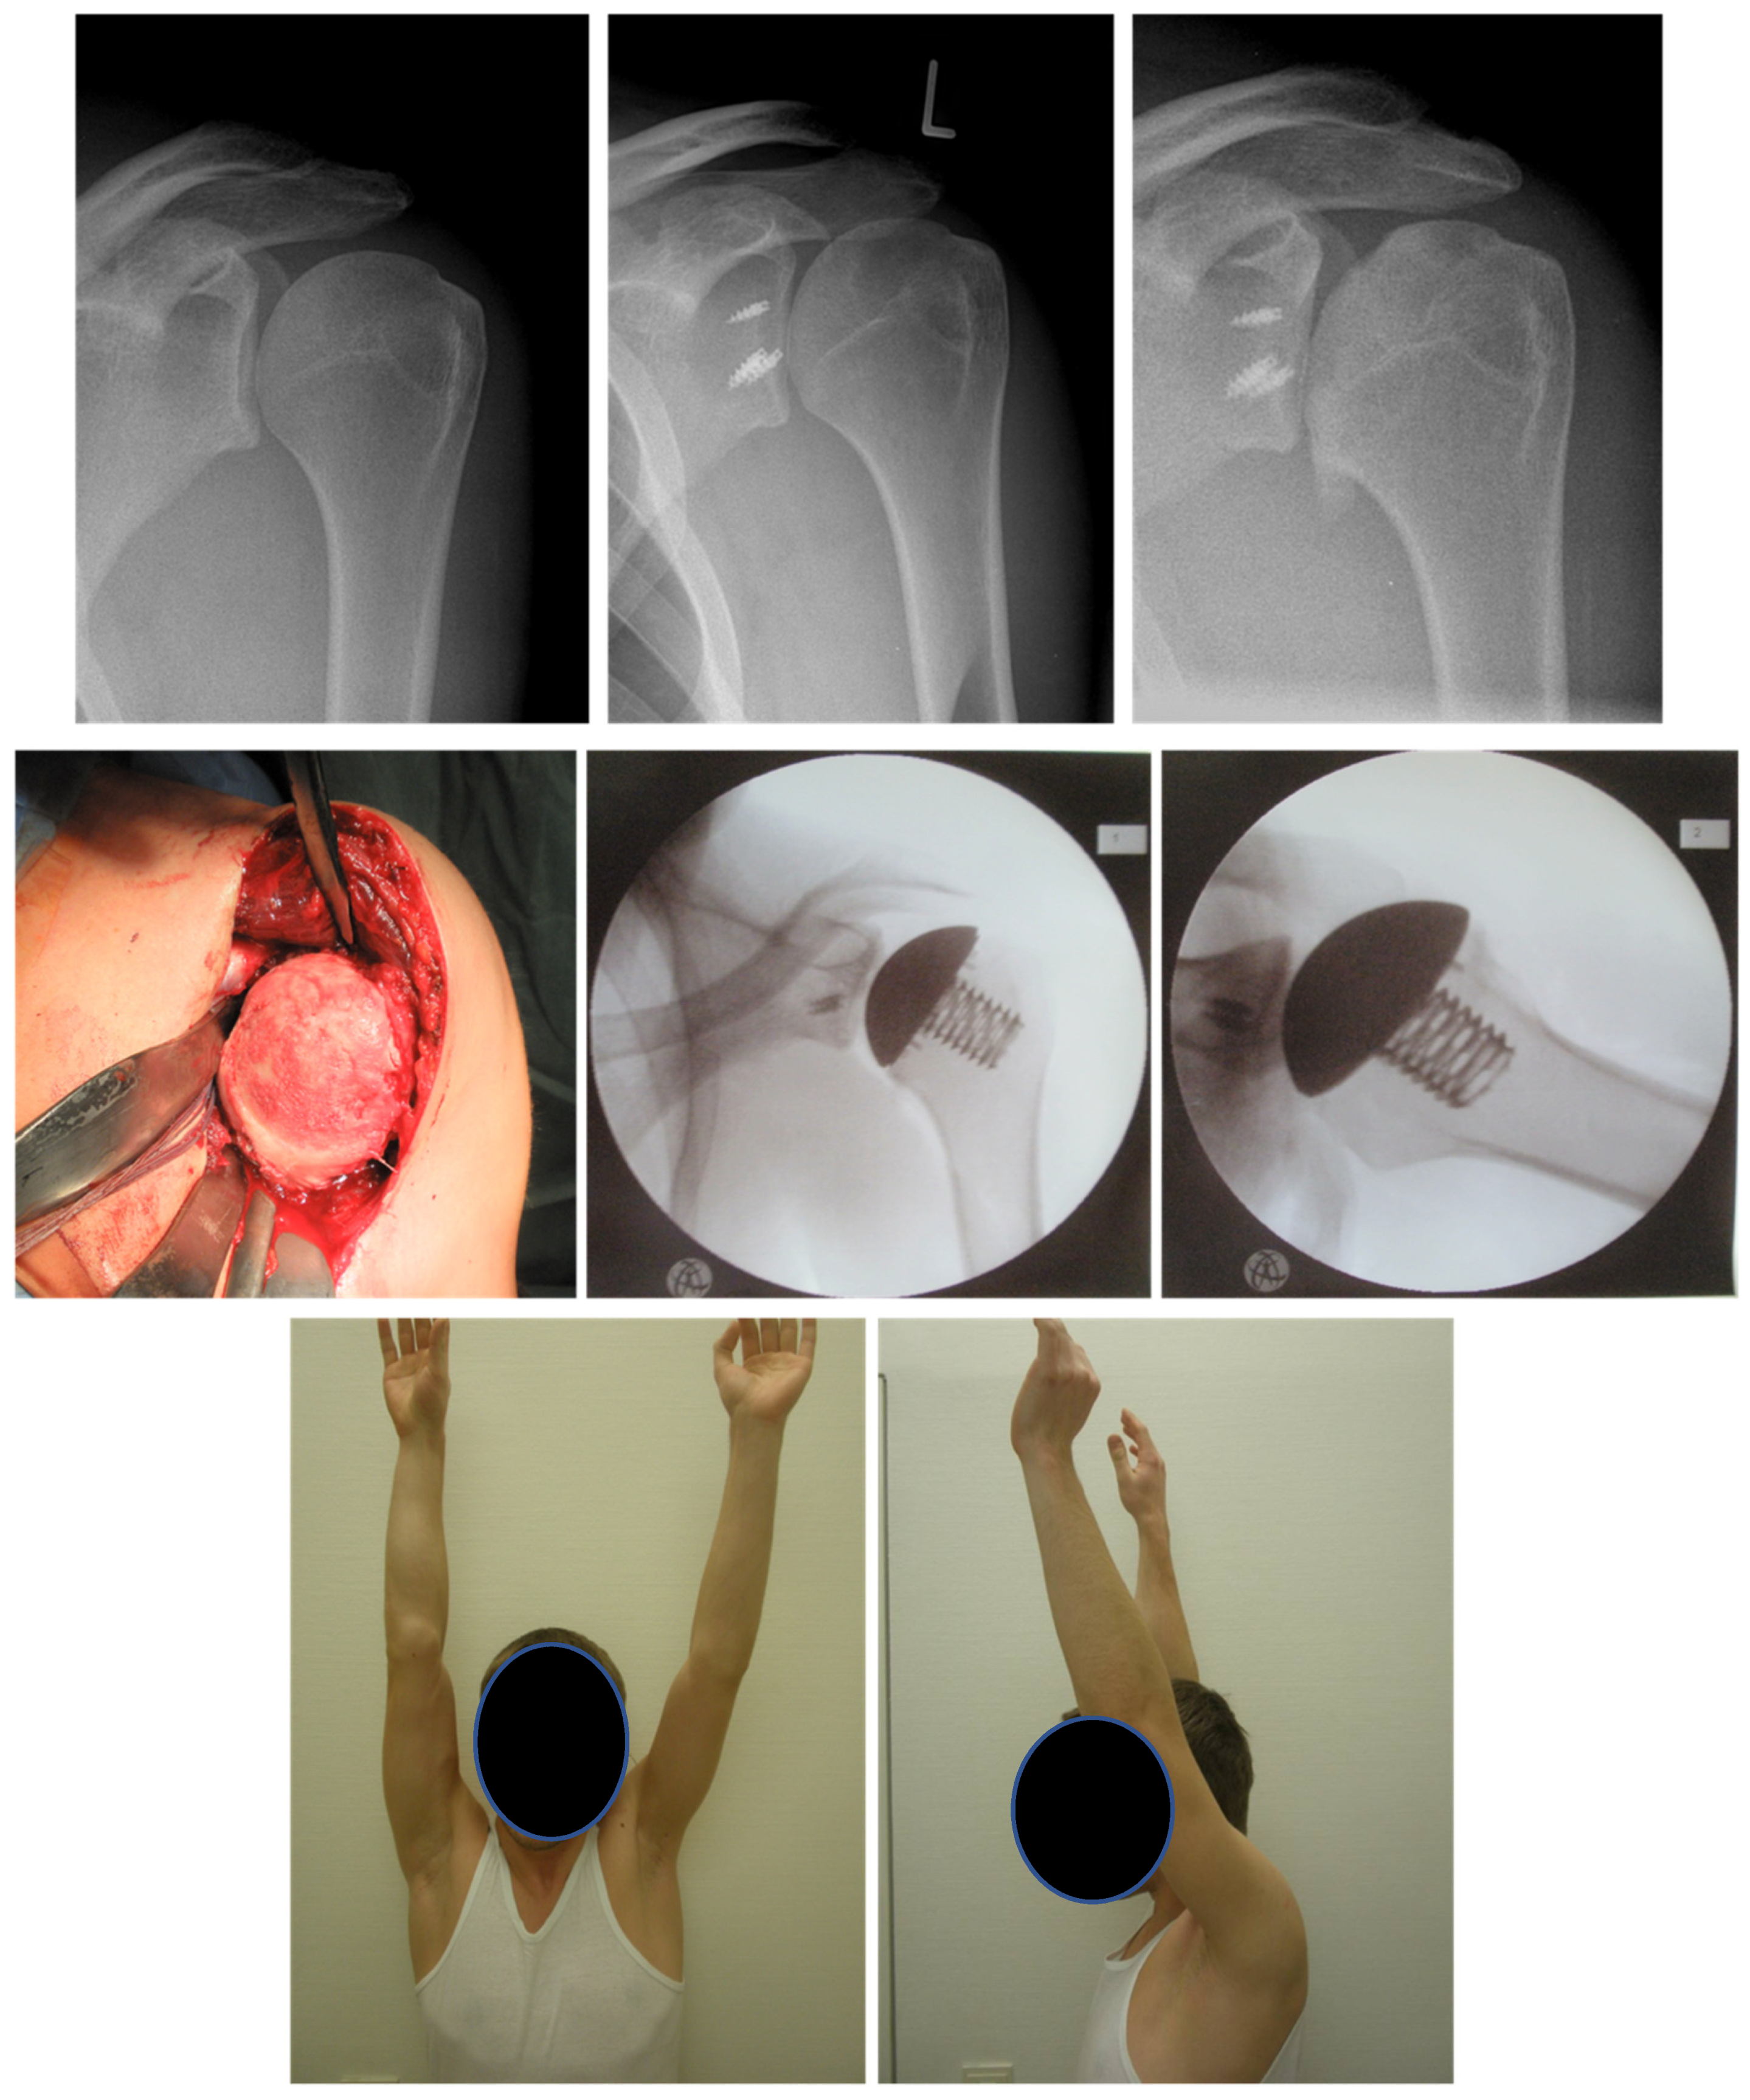

6.3. Arthroscopic Debridement and Arthrolysis

6.4. Arthroplasty